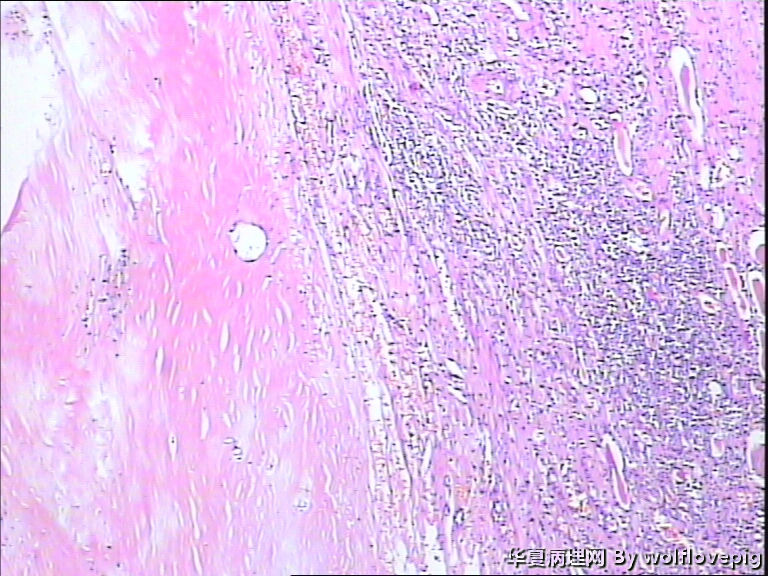

男,70y,左腰痛一年,反复血尿1月,坐肾区轻叩痛。

• 求助!肾脏包块!图1

图1

大体图片有些让人担心。镜下图片更倾向是良性病变。主要为对坏死组织的反应。

图片质量非常不好,显微镜下的图片几乎没法观察, 看大体标本还是不能除外肿瘤性病变,能不能采一些高质量的图片?

炎症性病变